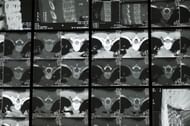

Tarlov cysts can be challenging to diagnose as they may not cause any symptoms, and their appearance on MRI scans may be similar to other spinal abnormalities.

A detailed medical history, physical examination, and imaging tests, such as MRI or CT scans, may be used to diagnose perineural cysts.